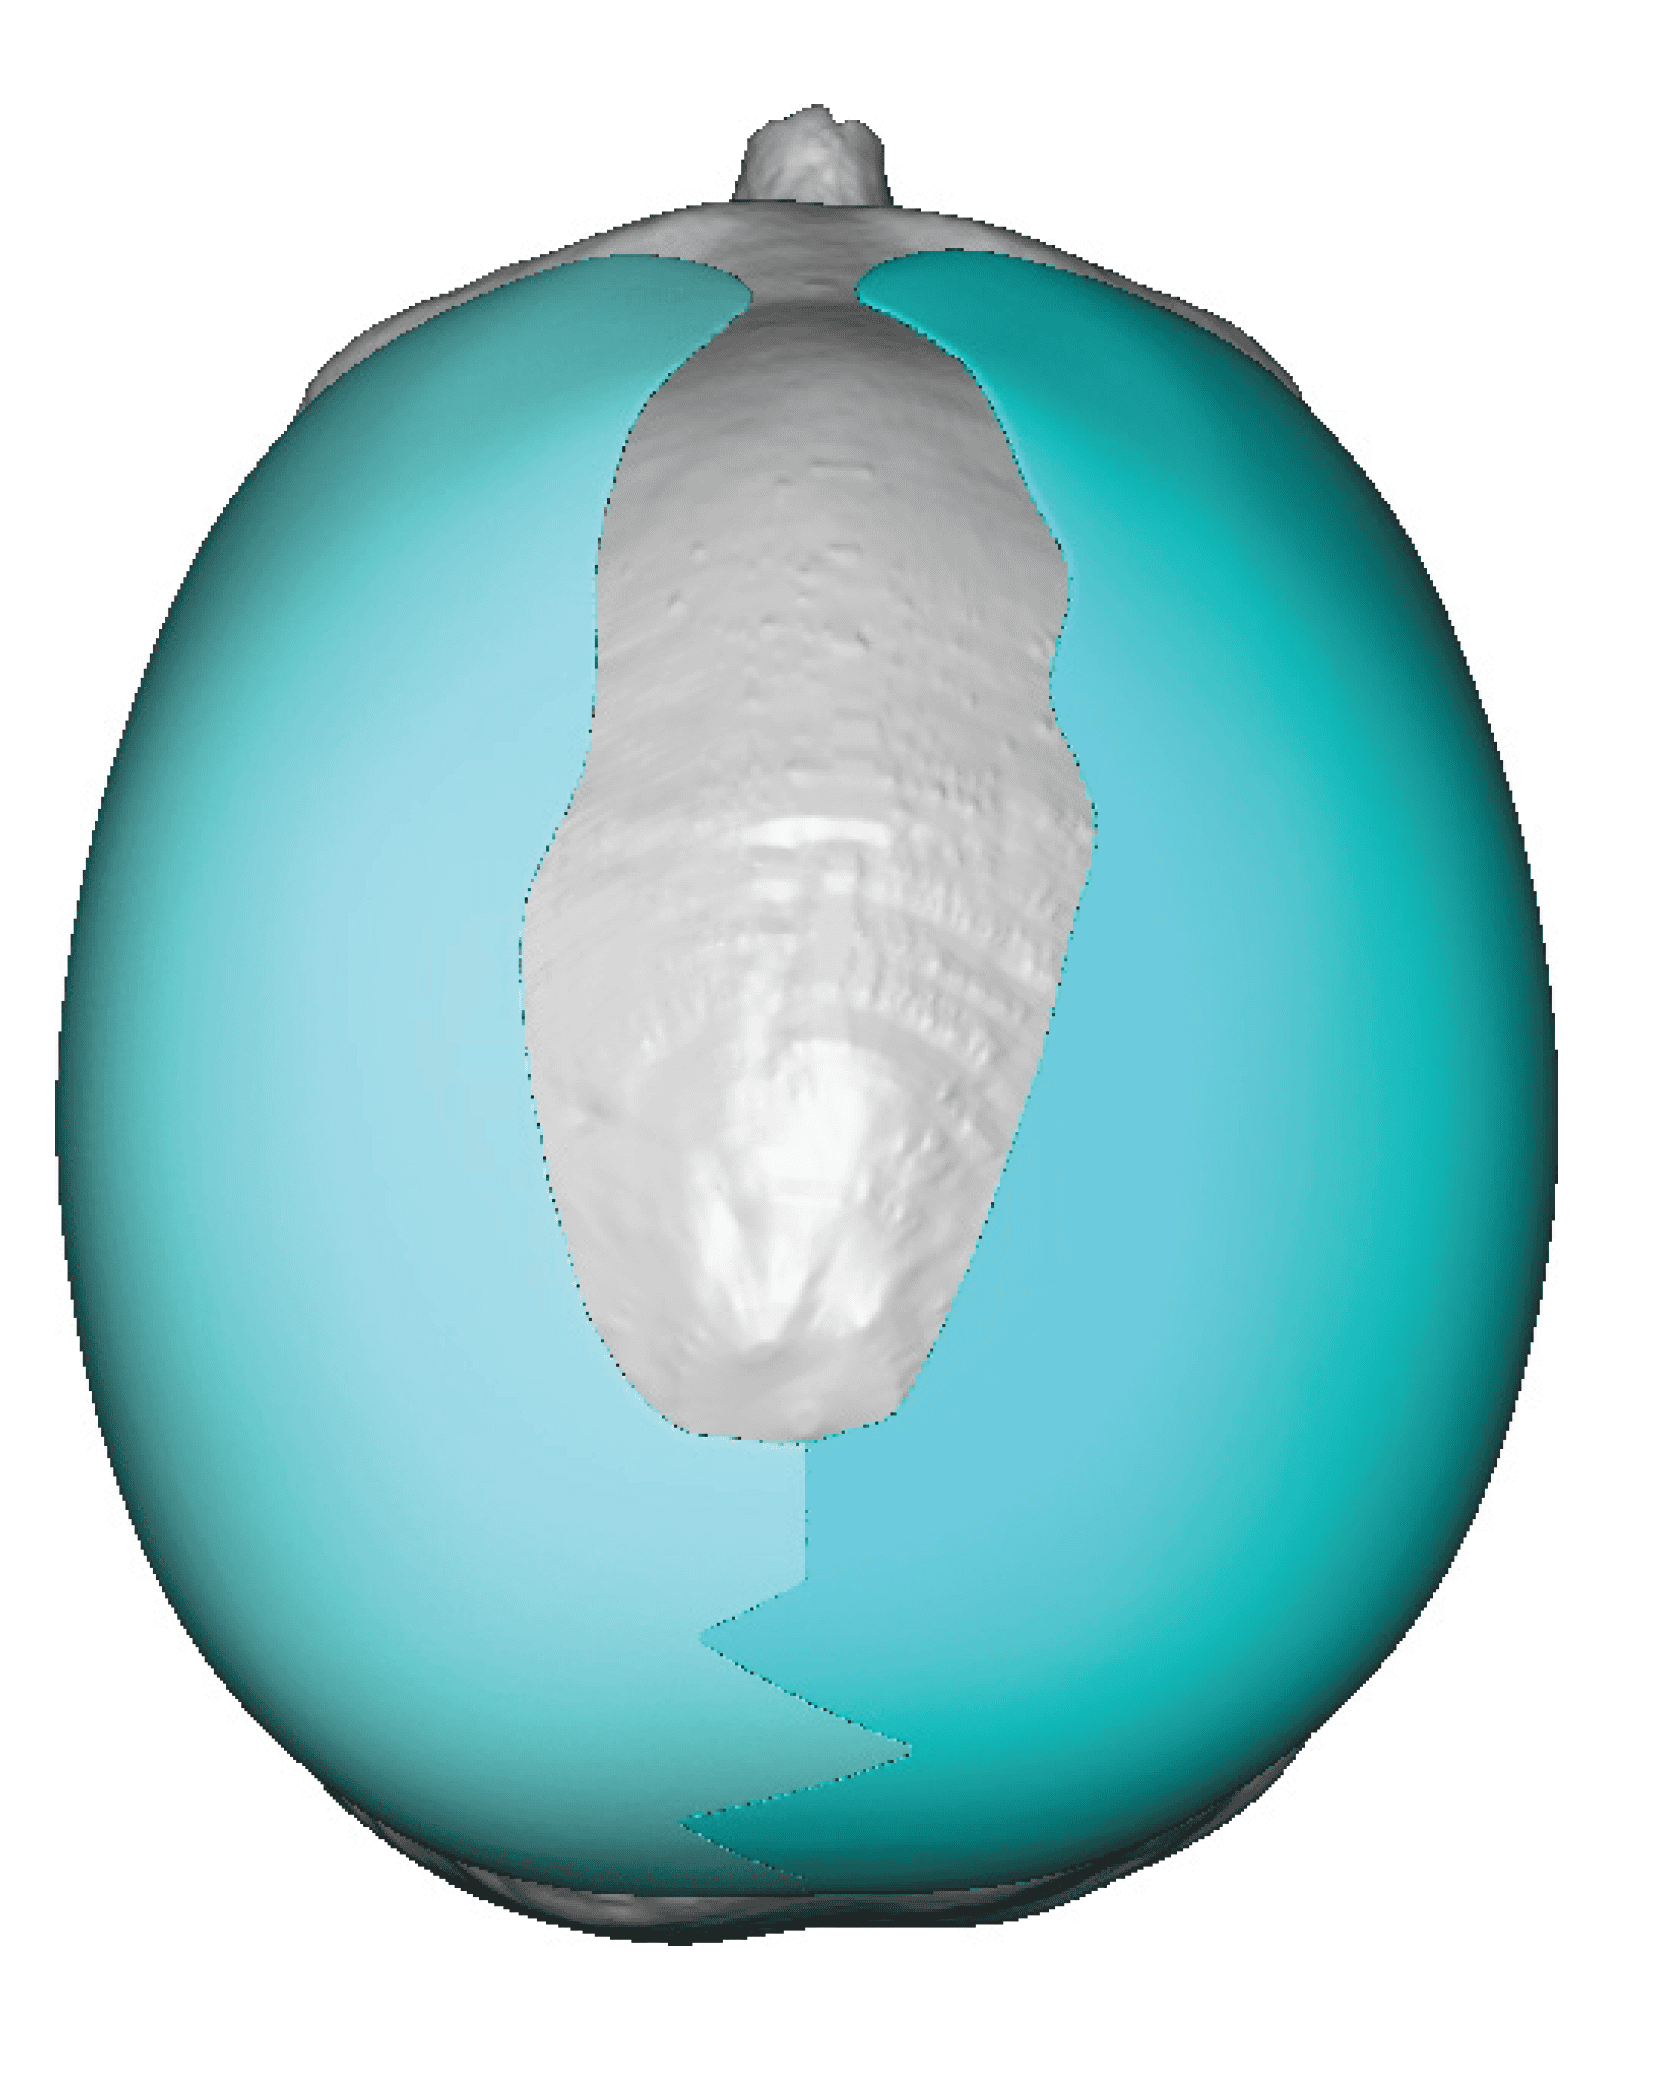

Desire for major head reshaping with a taler and wider head shape.

Placement of large two piece custom skull implant through a sagittal scalp incision.

Desire for major head reshaping with a taler and wider head shape.

Placement of large two piece custom skull implant through a sagittal scalp incision.